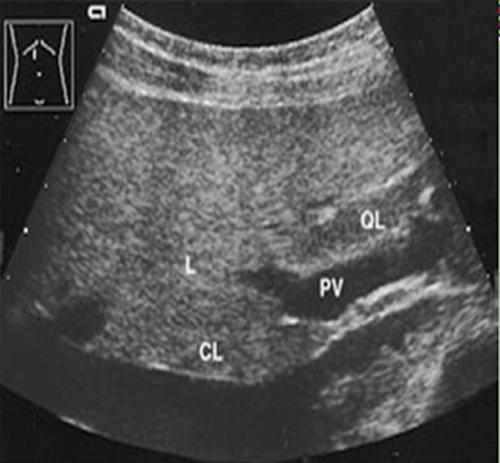

found on the inferior, posterior side of the liver. The caudate lobe is bordered by the inferior vena cava posteriorly and the ligament venosum anteriorly. The hepatic veins run between the lobes and segments. The portal veins run centrally within the segments. The ascending portion of the left portal runs in the left intersegmental fissure.

Give an anatomical description of the medial left liver lobe.

also called the Quadrate lobe, is bordered by the porta hepatis posteriorly, laterally by the gallbladder fossa and ligament terres.

What lies at the anterior border of the caudate lobe?

left portal vein

What seprates the caudate from the left liver lobe?

ligament venosum